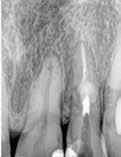

3. ábra: A gyökértömés elkészítése során készített felvétel.

4. a–b. ábra: A reszorbciós üreg Biodentine-nel való feltöltése. Intraoperatív (a) és radiológiai felvétel (b). – 5. ábra: Az öt hónappal később látható állapot. Nem észlelhetők gyulladás fennállására utaló jelek.

A gyökércsatorna feltágítását és tisztítását hagyományos kemomechanikai protokoll szerint végeztük. Először passzívan levezetett kézi tűk segítségével a gyökércsatornát teljes munkahosszon szondáztuk, ezt követően gépi tágítókkal feltágítottuk, ezalatt nátrium-hipoklorittal öblítettünk, amelyet manuális agitációval aktiváltunk. A gyökércsatorna méretre történő tágítását követően, a következő átöblítőszereket alkalmaztuk: 3 percen keresztül ultrahanggal aktiváltunk 5,25%-os NaOCl oldatot, amelyet közben többször frissítettünk a csatornában, majd váltott átöblítés (17%os EDTA, 5,25%-os NaOCl) a smear layer eltávolítása céljából. Végső átöblítésként 5 percen keresztül ismét 5,25%-os NaOCl oldatot alkalmaztunk, amelyet ultrahanggal aktiváltunk és folyamatosan cseréltünk. A kemomechanikai megmunkálás és az átöblítőszerek alkalmazása során az elszívást a reszorbciós üreg széléhez helyeztük annak érdekében, hogy a kifolyó kémiai hatású szerek ne tudják a környező csont állományt roncsolni.

A gyökértömés elkészítése során meleg vertikális kompakciós technikát alkalmaztunk, sealerként pedig CeraSeal-t (Meta Biomed; 3. ábra) használtunk. A reszorbciós üreget Biodentine-nel (Septodont; 4. a–b ábra) töltöttük fel. A reszorbcióval érintett területtől koronális irányba elhelyezkedő csatornaszakaszt pedig tisztán meleg guttaperchával kezeltük. Ezt követően a lebenyszéleket visszafektettük, és varratok behelyezésével eredeti pozíciójuknak megfelelően rögzítettük. A koronai részt kompozit tömőanyag segítségével állítottuk helyre. Kontrollvizsgálatra 5, illetve 30 hónappal később került sor (5. ábra). A csontos telődés jelei már 5 hónap után észlelhetők voltak (6. a–c ábra). A 30 hónappal később végzett kontroll során sem találtunk csontban lévő lézióra, törésre vagy egyéb pathológiás elváltozásra utaló jeleket (7. a–b ábra)